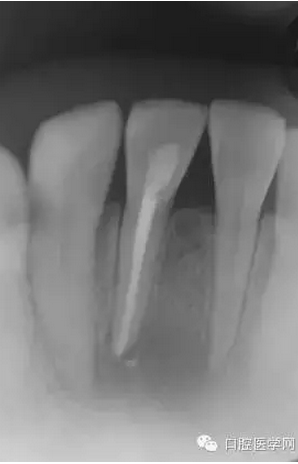

23歲女性患者,下頜右前牙的唇側(cè)有嚴(yán)重腫脹和疼痛。相應(yīng)部位有過(guò)外傷史,但記不起是什么時(shí)候了。放射線照片顯示以右下頜中切牙為中心,有波及右下側(cè)切牙及左下中切牙的大范圍的根尖周病變,臨床檢查時(shí),無(wú)齲壞,只發(fā)現(xiàn)右下中切牙略有變色,牙髓活力檢查(電子牙髓檢查及冷檢查)發(fā)現(xiàn),右下中切牙無(wú)反應(yīng),而鄰近齒表現(xiàn)為正常。判斷大范圍的根尖周病變的原因是受過(guò)外傷的右下中切牙的牙髓壞死,受周邊環(huán)境影響,發(fā)展為急性根尖周膿腫。

(圖 1) 初診的放射線照片